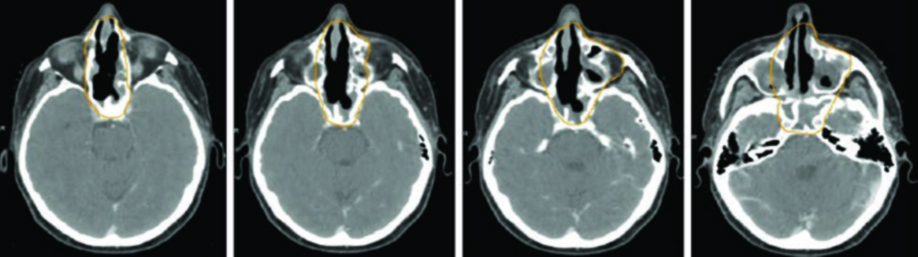

Alguns padrões de disseminação merecem atenção especial. ENB, SNUC e SNEC surgem na cavidade nasal superior e invadem facilmente a lâmina cribriforme em direção à fossa craniana anterior. Essas regiões precisam ser incluídas no volume alvo. Já os cânceres do seio maxilar podem invadir a cavidade nasal pela parede medial porosa, a gengiva maxilar pela parede lateral do antro, a fossa infratemporal ou pterigopalatina por extensão posterior, ou a órbita por extensão superior direta ou via seios etmoidais.

A TC de alta resolução dos seios paranasais com contraste IV e cortes finos de 1–2 mm é ideal para visualizar erosão cortical óssea precoce. A RM com contraste IV e sequências com supressão de gordura, em cortes finos, é superior para avaliar extensão em partes moles, extensão intracraniana, invasão perineural e envolvimento dos forames e canais dos nervos cranianos. O PET/CT complementa o estadiamento ao identificar linfonodos suspeitos e doença metastática.

O GTV deve ser delineado usando todas as informações clínicas relevantes de endoscopia, TC, RM e PET. O CTV de alto risco deve cobrir todos os sítios iniciais de doença e regiões potenciais de disseminação subclínica. Todas as imagens pré-operatórias devem ser avaliadas para garantir que o volume tumoral inicial esteja coberto.

A RM deve ser usada em todos os casos para auxiliar o delineamento, exceto quando contraindicada. Carcinomas adenoides císticos são altamente neurotrópicos, portanto os volumes devem cobrir nervos aferentes e eferentes locais até a base do crânio. ENB surge na cavidade nasal superior e tende a invadir a lâmina cribriforme e fossa craniana anterior precocemente.

| Cavidade nasal (CEC, ENB, SNUC, SNEC, melanoma) | Superior | Lâmina cribriforme (se intacta) ou enxerto dural. Margem dural de 5 mm quando cribriforme envolvida ou extensão intracraniana macroscópica |

| Inferior | Palato duro | |

| Medial | Incluir toda a cavidade nasal | |

| Lateral | Parede medial do seio maxilar ipsilateral para casos localizados | |

| Posterior | Lâminas pterigoides, fossa pterigopalatina, seio etmoidal e seio esfenoidal | |

| Nervos | Ramos de CN I, CN V1 e CN V2 incluindo nervos nasociliar e nasopalatino | |